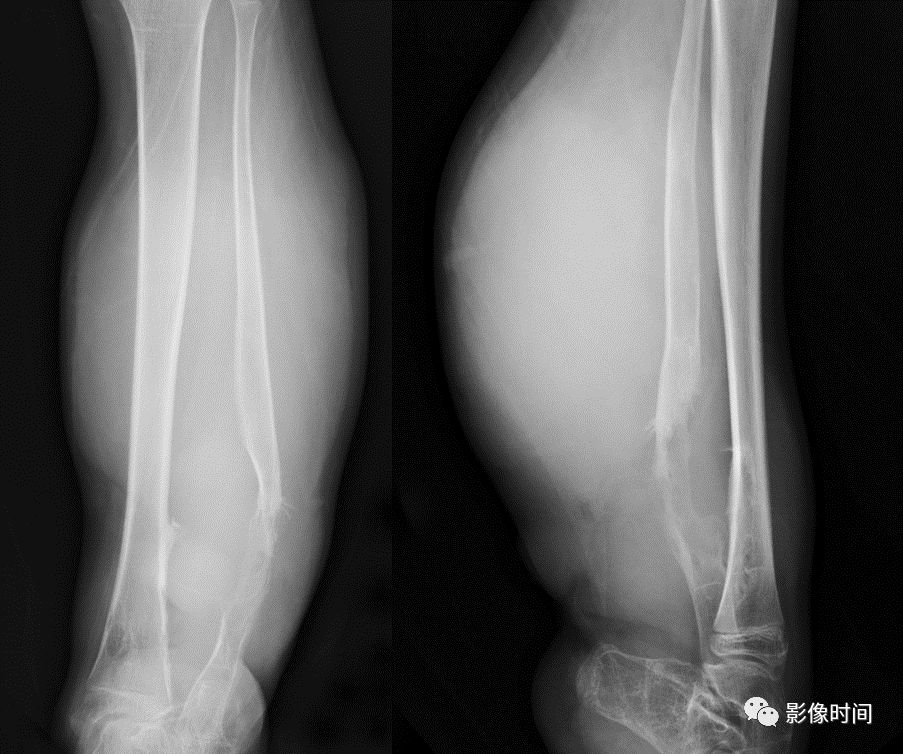

八、软组织肿块

软组织肿块是诊断恶性骨肿瘤重要依据。X 线平片、CT 及 MRI 均可用于软组织肿块的评估,X 线平片显示软组织肿块作用有限,表现为局部软组织密度增高影,边缘隐约可见(图 55),CT 和 MRI 显示软组织肿块明显优于 X 线平片(图 56、图 57),可清楚显示软组织肿块的大小、边缘轮廓外,还可清晰显示软组织肿块内部病理变化,对肿瘤定性诊断有帮助作用。

对于软组织肿块影像学需重点观察其边缘、密度/信号均匀性,是否伴有钙化或骨化,增强扫描后强化特点以及瘤周是否伴发水肿等表现。

图 55  软组织肿块:恶性骨巨细胞瘤

图 56  软组织肿块:骨软骨瘤恶变

图 57  软组织肿块:骨淋巴瘤